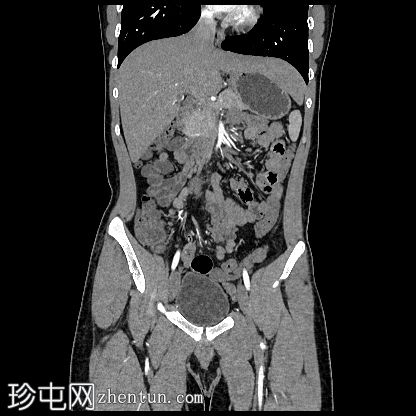

冠状位增强扫描

动脉期

阴茎:发育良好。阴茎海绵体和尿道海绵体均存在。

阴囊:双侧均存在,但空虚。

左侧腹股沟深环可见一裂隙,大网膜脂肪由此突出至左侧阴囊。裂隙大小约20毫米。

盆腔左侧可见一形态良好的子宫样结构(57 x 17毫米),开口于前列腺尿道。

右侧睾丸位于盆腔右侧,膀胱与直肠之间。大小:56 x 29 毫米。

左侧睾丸位于盆腔中线左侧,膀胱上方,子宫底旁。该结构附着于从左侧腹股沟管延伸出的索状结构上。大小:38 x 22 毫米。

患者有双侧隐睾病史。CT和MRI图像显示发育良好的子宫和两个睾丸,均位于盆腔内。子宫内膜腔开口于前列腺尿道。

该患者表型为男性,阴茎发育良好。精液分析显示无精子症。结合影像学检查结果,最可能的诊断是持续性苗勒氏管综合征。这是一种男性假两性畸形,由子宫内抗苗勒氏管激素(AMH)分泌不足引起。AMH或其信号通路的缺乏导致苗勒氏管衍生结构的持续发育。